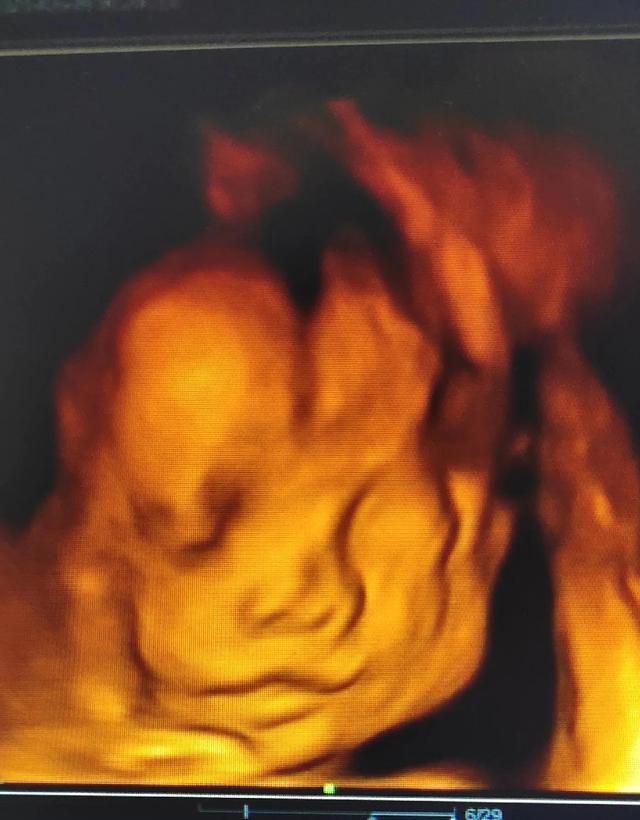

#你好,新生活#已经进入孕晚期。我每天都睡不好。不能多吃,少油少盐,少吃甜食。最重要的是经历耻骨疼痛和漏尿。有些人可能手脚浮肿,晚上胎动频繁。我等不及要住厕所了。很难翻身。我不能穿着袜子和鞋子弯腰。洗头很难。大多数人从孕中期就会有妊娠纹。为了孕育新的生命,每个母亲都是伟大的,这让我更加意识到父母养育我的艰难,也更加意识到为人父母的艰难。好在老公婆婆对我很好,让我减轻了一些负担。即使很努力,也对宝宝充满期待。我希望他健康平安地来到这个世界。我的妈妈会永远爱你,我的宝贝!